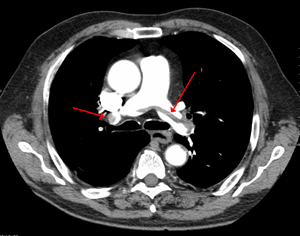

Chest spiral CT scan with radiocontrast agent showing multiple filling defects both at the bifurcation ("saddle" pulmonary embolism) and in the pulmonary arteries.

Large saddle embolus seen in the pulmonary artery (white arrows).